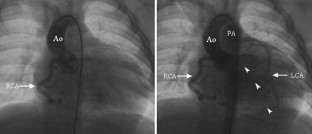

Fig. 3